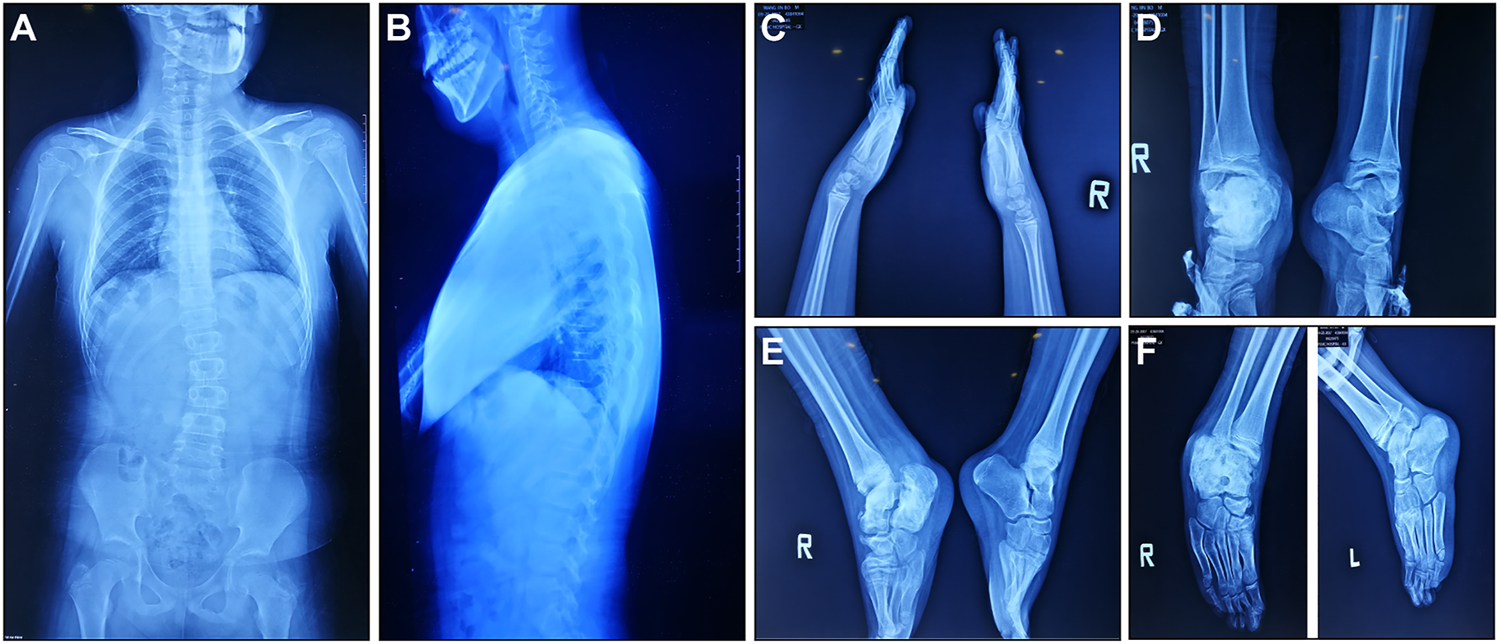

According to medical history survey, the patient has developed bilateral ankle swelling and fractures since 18 months. His intellectual development was significantly behind peers in motor and language development. Multiple fractures to his right ankle and swelling of his ankle and knee limited his movement. X-ray result showed scoliosis, osteomyelitis-like changes in the right ankle, bone deformation, bone destruction on multiple joints, and osteomyelitis-like changes after partial vertebral deformation (Figure 1).

FIGURE 1

X-ray manifestations of the recruited CIPA patient. (A,B) Front and side images of the torso. (C) Hands and wrists. (D–F) Ankles in different angles.